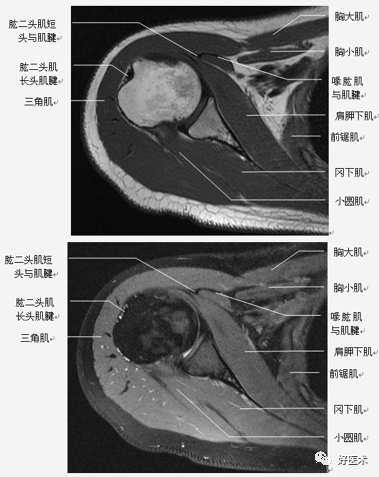

肩关节是一个复杂的关节,它由多个关节、多块肌肉、多条韧带之间相互作用,形成身体中一个独特的区域。熟悉相关解剖是快速诊断、成功手术必备要素,尤其是对于刚开始做肩关节手术的医师更为重要。今天采用高清图谱讲解肩关节影像解剖,值得学习借鉴!

肩关节固有肌群

肩关节非固有肌群:斜方肌、背阔肌、肩胛提肌、菱形肌、前锯肌、胸大肌、胸小肌、锁骨下肌。